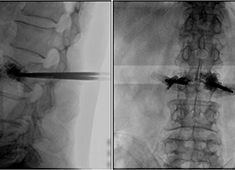

C臂機在打骨水泥時是怎么使用的(PKP手術(shù)記錄)

在打骨水泥時通常要借助C臂機來進行,具體是如何使用的呢?下面通過南京醫(yī)科大學(xué)第二附屬醫(yī)院的一則手術(shù)案例來深入學(xué)習(xí)。首先將患者處于俯臥位,然后利用普愛大平板C臂機擺位靈活的特點,快速定位椎弓根位置...